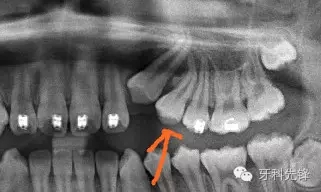

從X片上可以發(fā)現(xiàn)根尖1/3約有120°彎曲。

可以看到牙槽窩里面有一個斷根。